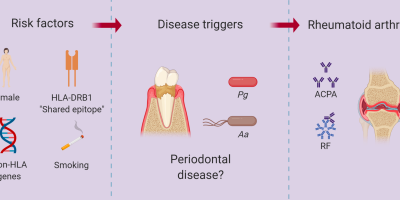

Periodontitis Unveils Deeper Relationship to Rheumatoid Arthritis

The connection between periodontitis and rheumatoid arthritis is undeniable. Treating or preventing periodontal disease may lower the ...